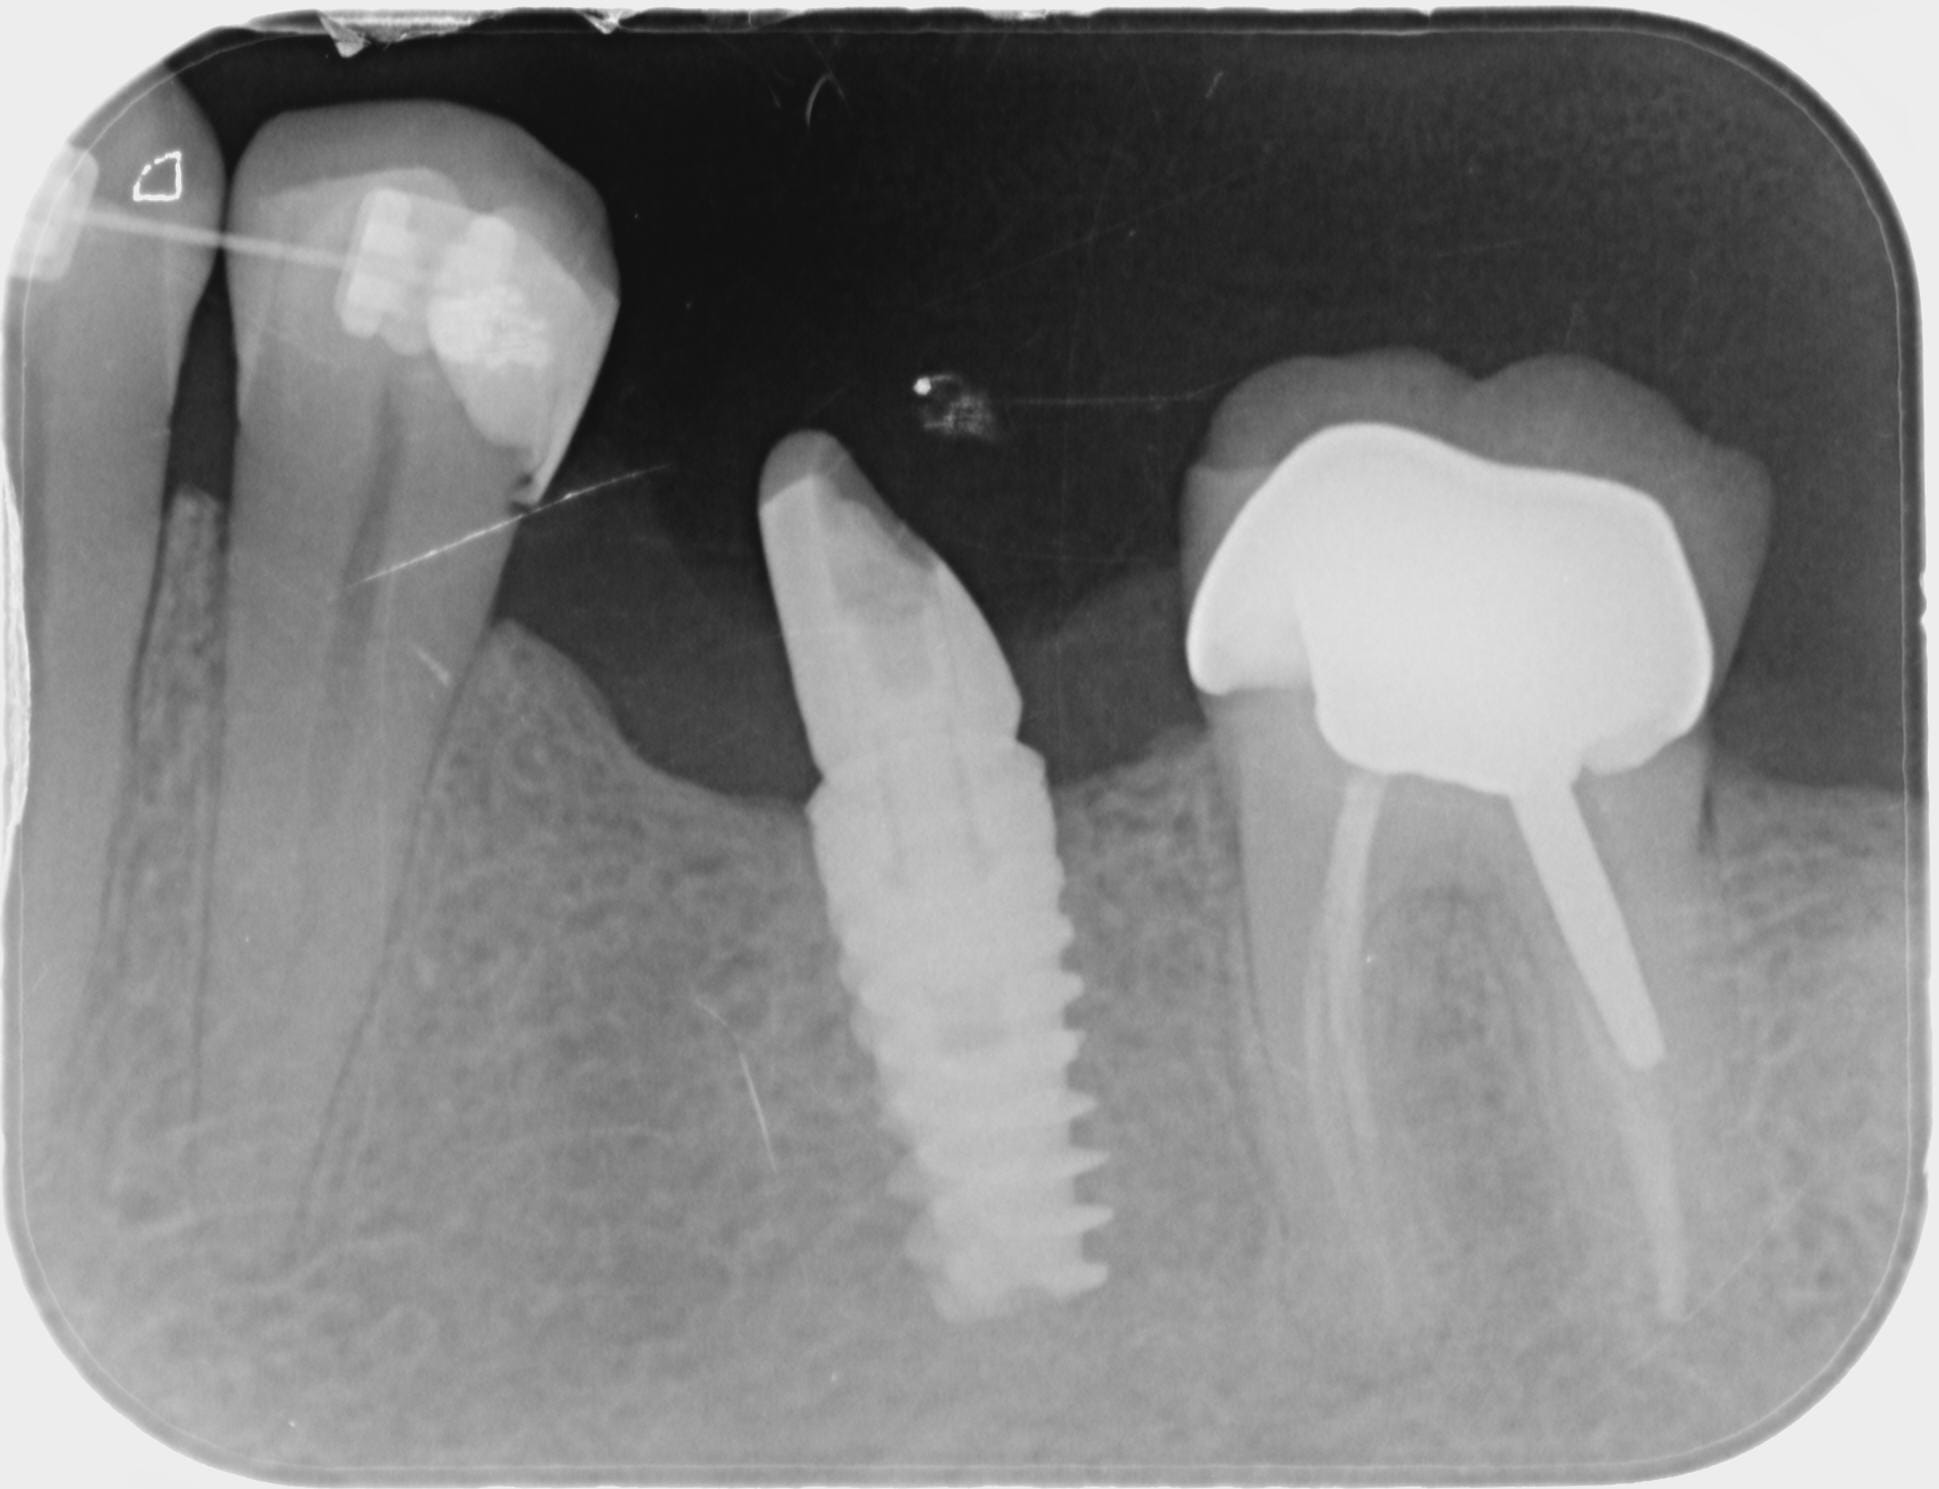

Au fait, l'implant a été posé il y a entre 10 et 15 ans

c'est un SPI Alphabio...

http://whatimplantisthat.com/implant/spi-4/